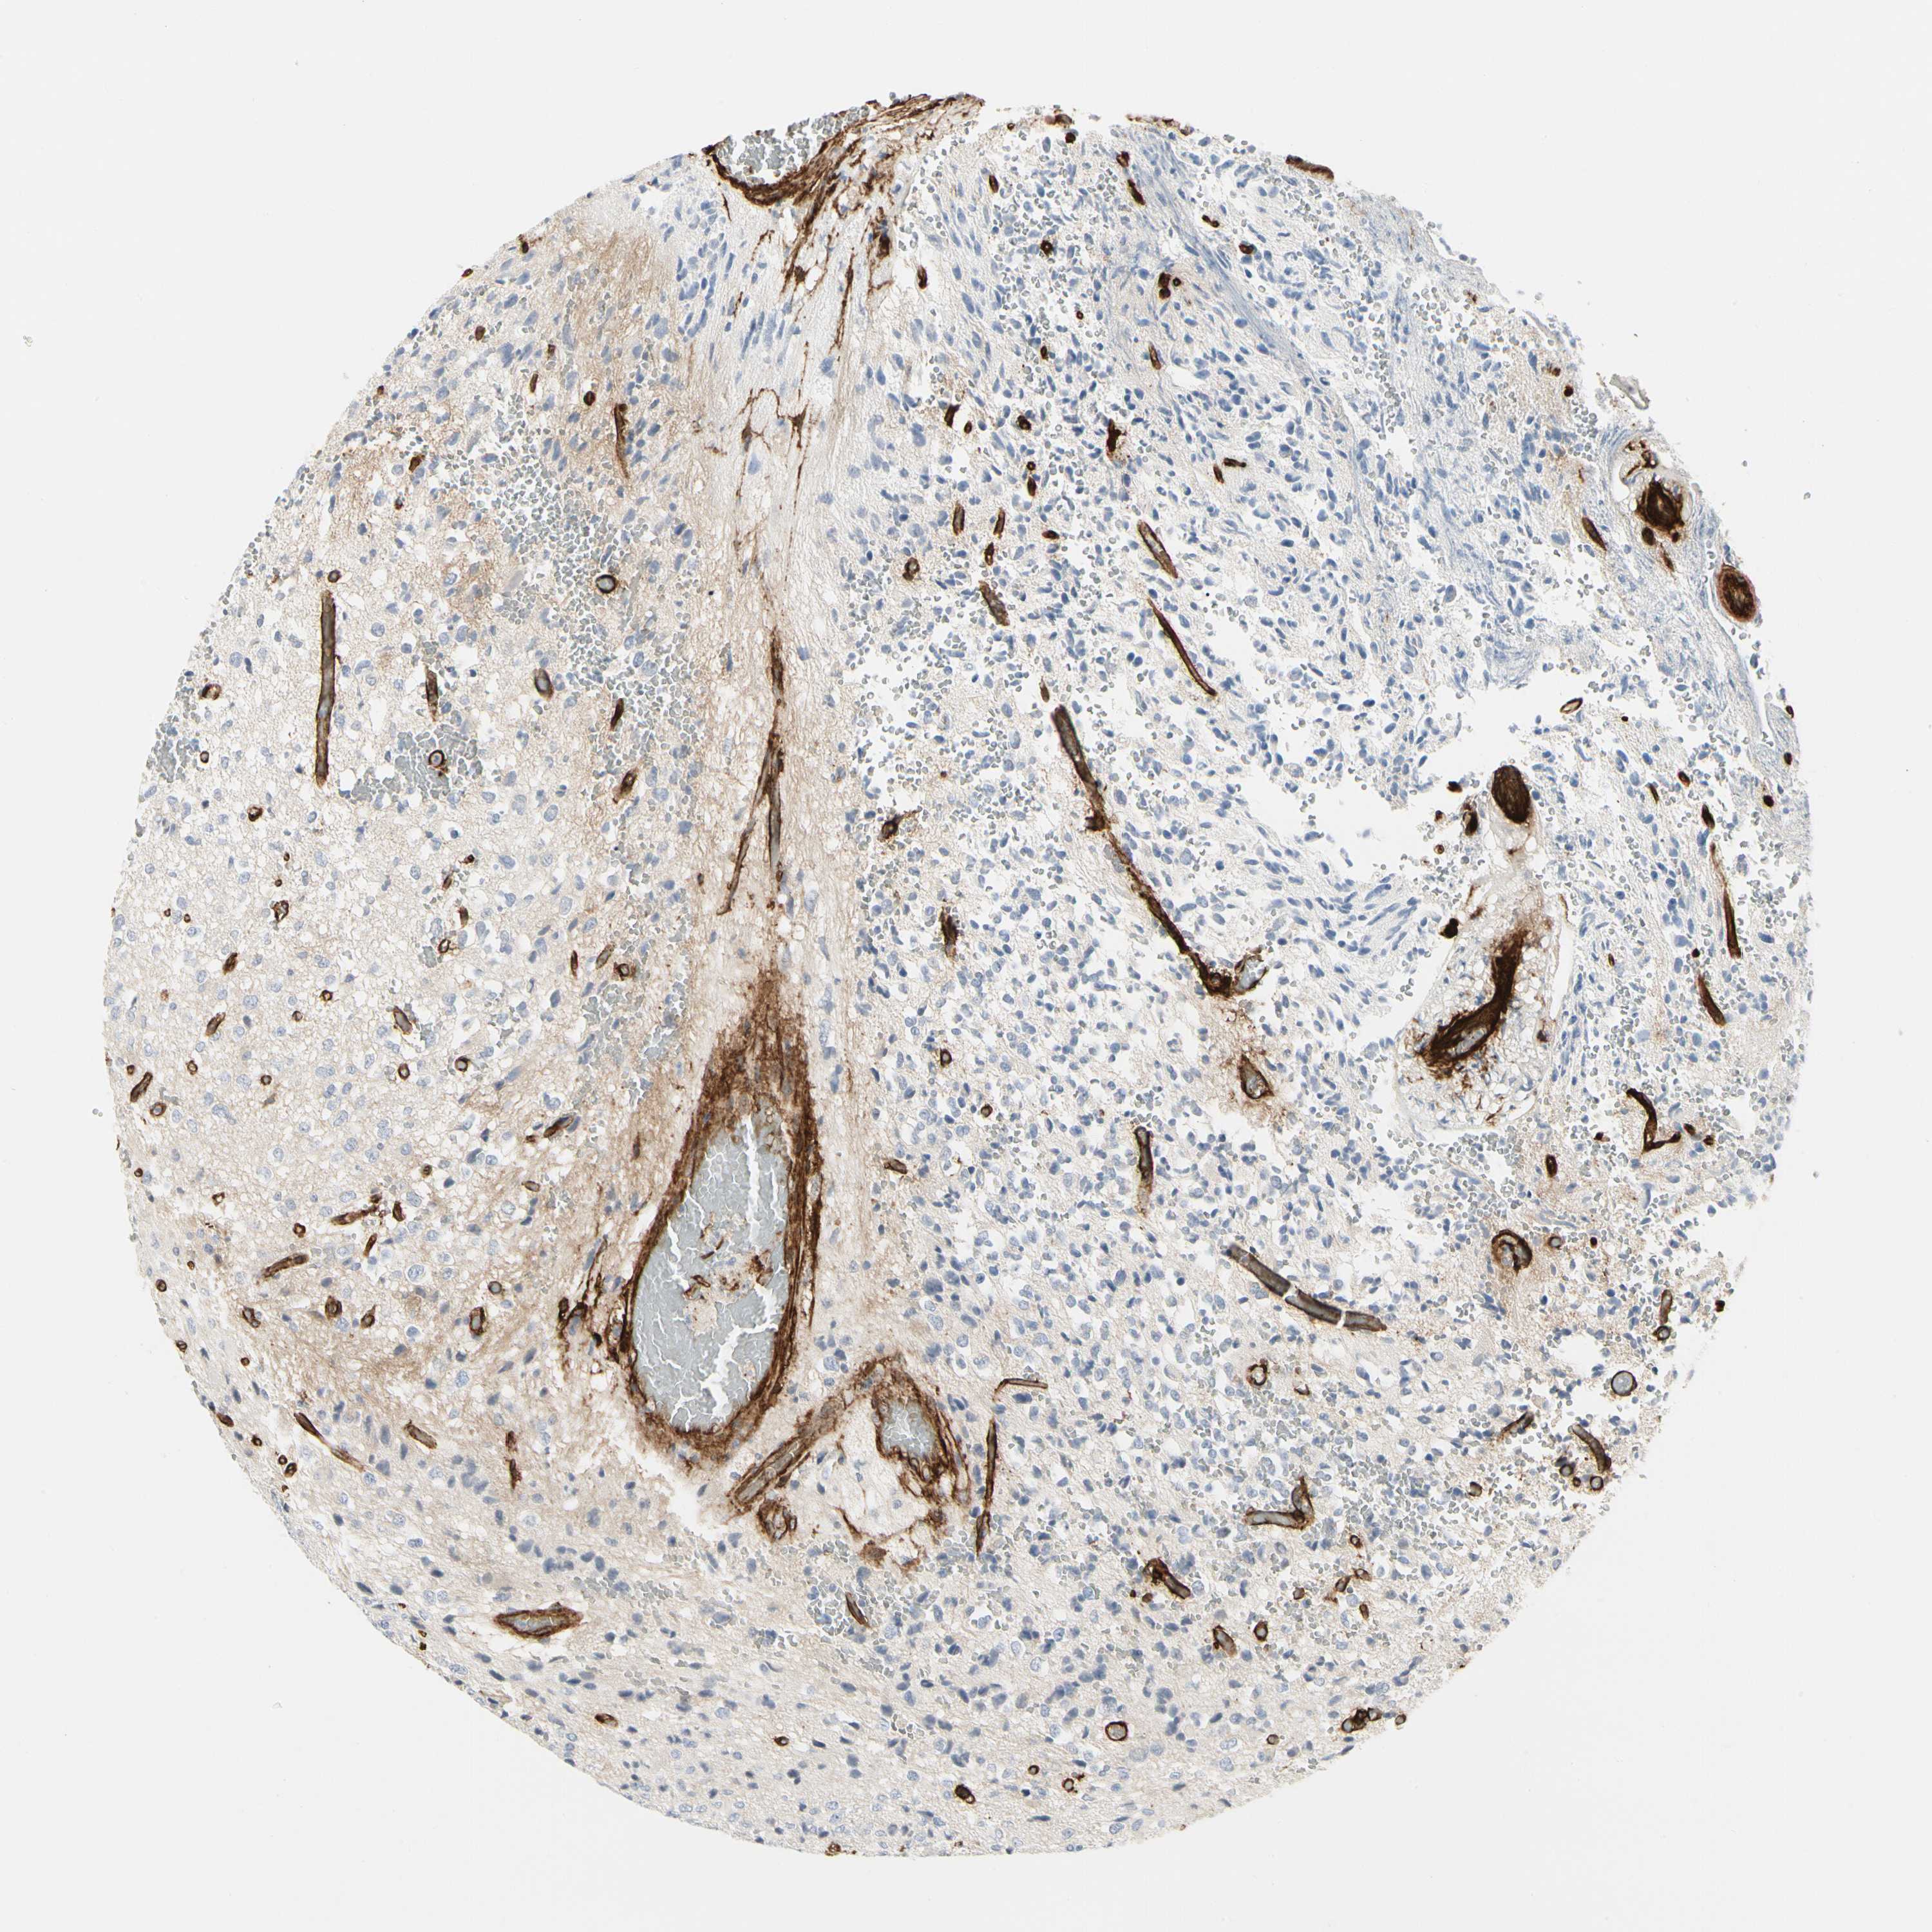

GLIOMA - Protein expressioni

A mouse-over function shows sample information and annotation data. Click on an image to view it in a full screen mode. Samples can be filtered based on level of antibody staining by selecting one or several of the following categories: high, medium, low and not detected. The assay and annotation is described here.

Note that samples used for immunohistochemistry by the Human Protein Atlas do not correspond to samples in the TCGA dataset.

Antibody stainingi

Antibody staining in the annotated cell types in the current human tissue is reported as not detected, low, medium, or high, based on conventional immunohistochemistry profiling in selected tissues. This score is based on the combination of the staining intensity and fraction of stained cells.

Each image is clickable and will lead to virtual microscopy that enables deeper exploration of all samples and also displays staining intensity scores, fraction scores and subcellular localization as well as patient and tissue information for each sample.

Antibody HPA008121

Antibody CAB032489

Staining

High

Medium

Low

Not detected

Intensity

Strong

Moderate

Weak

Negative

Quantity

>75%

75%-25%

<25%

None

Location

Nuclear

Cytoplasmic/membranous

Cytoplasmic/membranous,nuclear

Glioma, malignant, Low grade

Glioma, malignant, High grade